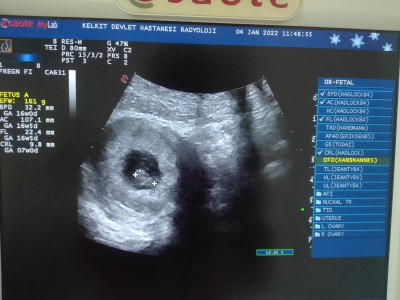

image

bak teyzesi bizim bıdıkda burda + varya iki + arasında

4 Ocak 2022 misafir yorumladı

Oyyy maşallah maşallah. Allah sağlıkla kucağınıza almayı nasip etsin inşallah . Darısı haftaya bana :)